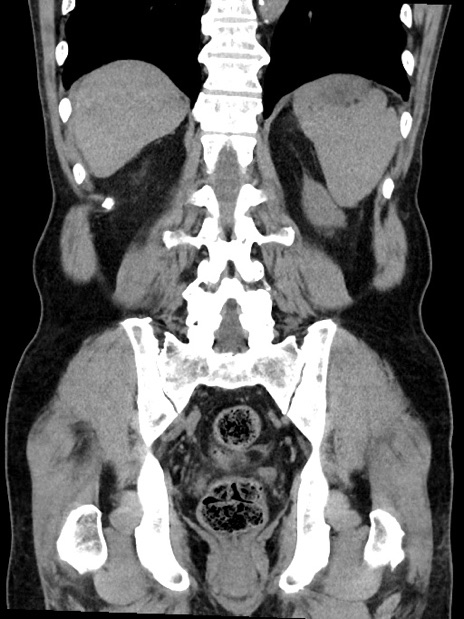

症例35(冠状断像)

【症例】70歳代 男性

【主訴】腹部膨満、嘔吐

【現病歴】昨日より腹部膨満感出現。本日増悪し、仙痛出現。嘔吐あり、受診。

【既往歴】糖尿病、胆摘後

【身体所見】BP 149/80mmHg、HR 74/min、BT 35.9℃、腹部:膨満、軟、圧痛なし。腸雑音減弱あり。上腹部正中切開瘢痕あり。

【データ】WBC 13500、CRP 1.72